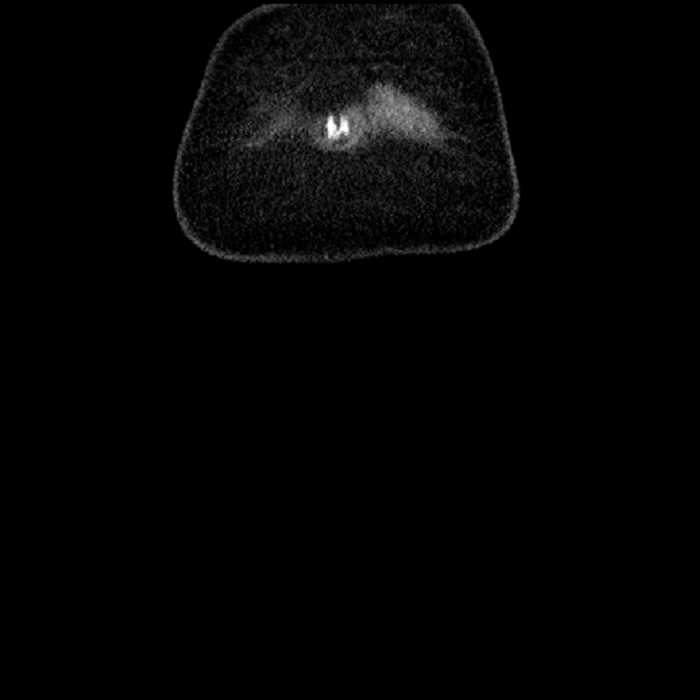

• Ankylosis of both sacroiliac joints

• High grade stenosis of the left common iliac artery, with the left internal and external iliac arteries remaining patent